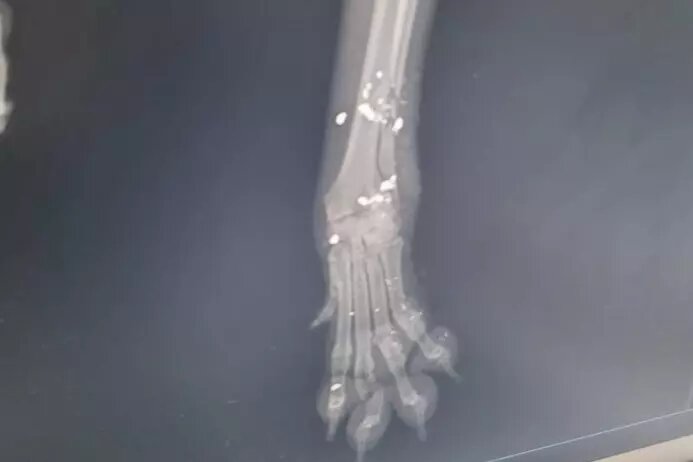

Там врачи сообщили, что ранение было огнестрельным. - Наша первоочередная задача — спасти бедное животное и попробовать сохранить лапку, так как дробью раздробило локтевую кость и пальцы на передней лапе. Собака в шоковом состоянии, — добавила Ольга.

- Наша первоочередная задача — спасти бедное животное и попробовать сохранить лапку, так как дробью раздробило локтевую кость и пальцы на передней лапе. Собака в шоковом состоянии, — добавила Ольга.